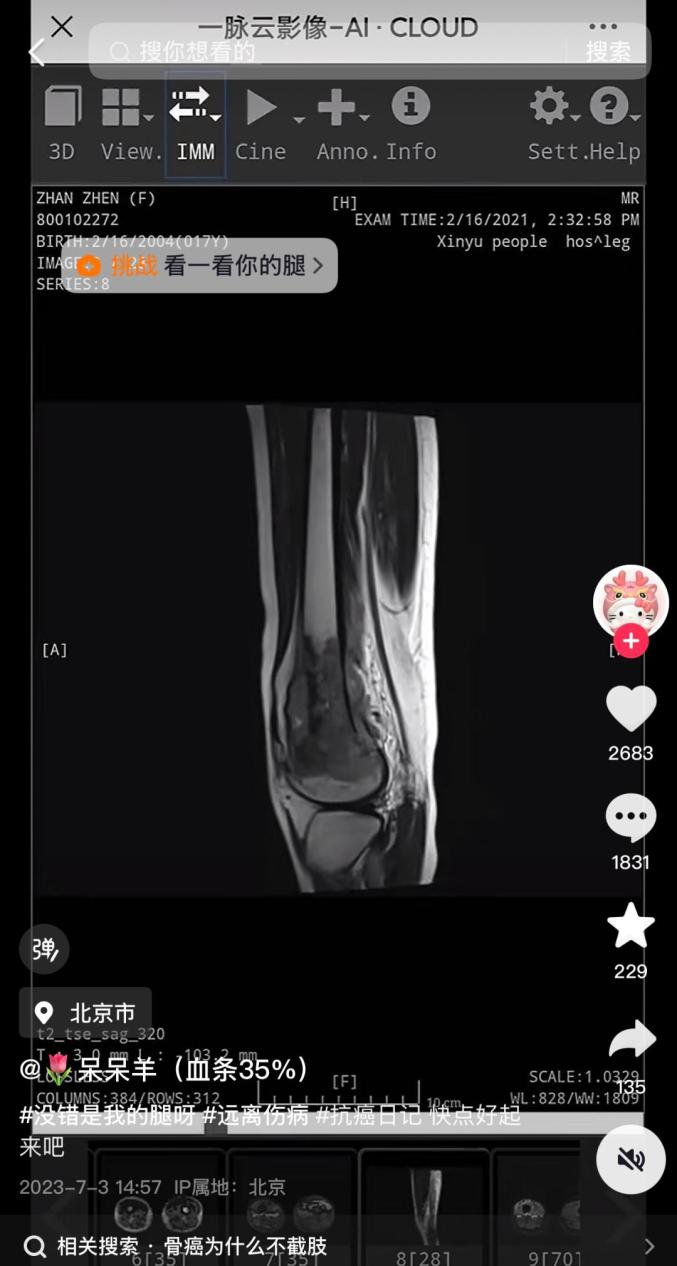

記者發(fā)現(xiàn),網(wǎng)紅“呆呆羊(血條35%)”短視頻賬號有18萬粉絲。2023年7月3日,“呆呆羊”更新首條內(nèi)容,視頻中“呆呆羊”發(fā)布了自己的診斷報告,時間為2021年2月16日。